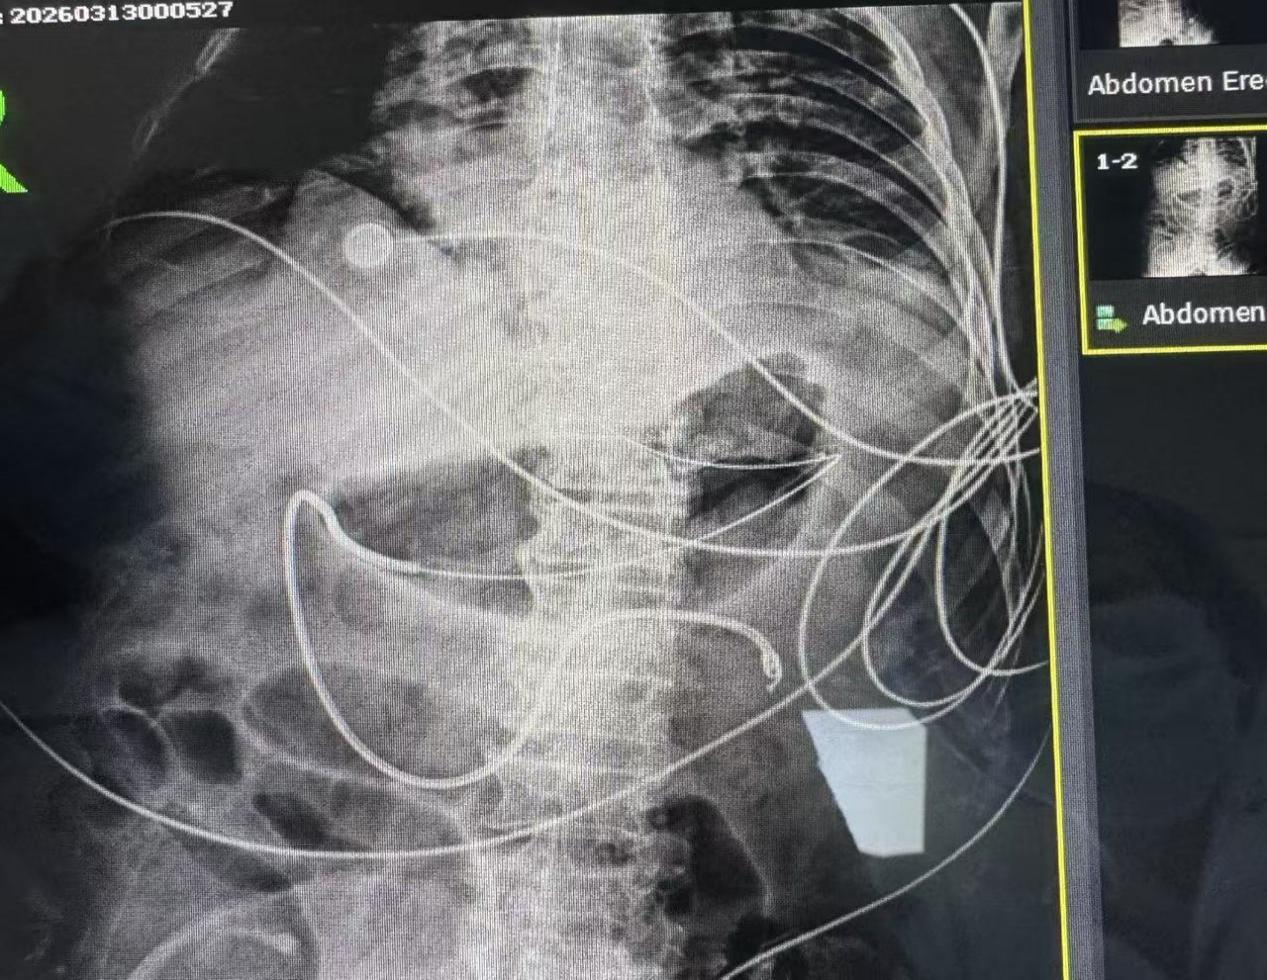

临床实战见实效,置管成功率100%

该技术已成功应用于临床,且无并发症。其中一例胆源性重症胰腺炎患者的救治成果尤为亮眼:该患者合并腹腔高压、胃肠麻痹,胃潴留量超300ml,无法经胃管喂养,常规鼻饲或加重病情。我院ICU护理团队果断实施床旁盲插鼻肠管操作,一次性成功将营养管置入空肠100cm处,顺利打通专属营养通道。

置管后成效立显:72小时内启动肠内营养,首日输注营养液患者无腹胀、腹压稳定;7日内营养达标率95%,血清白蛋白显著提升;无误吸、感染等并发症,患者2周后顺利过渡至经口饮食。截至目前,我院ICU已成功开展该技术3例,置管成功率100%、零并发症,充分验证了技术的安全性与有效性,彰显了我院医护团队的专业实力。